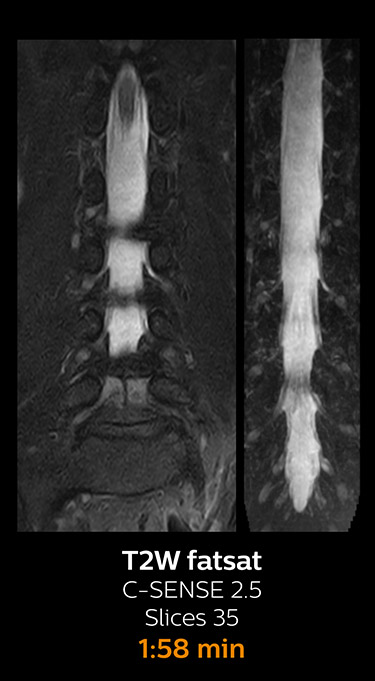

Fast MRI of lumbar spine

which corresponds to 34% reduction.

With Compressed SENSE, the scan time for the routine lumbar spine examination at KNC was reduced from 11:41 to 8:17 minutes,

MRI examination of the lumbar spine with Compressed SENSE

Ingenia 3.0T CX

Scan time 8:17 min. (was 11:41 min. without Compressed SENSE)